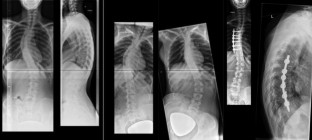

Abb. 1

Abb. 2